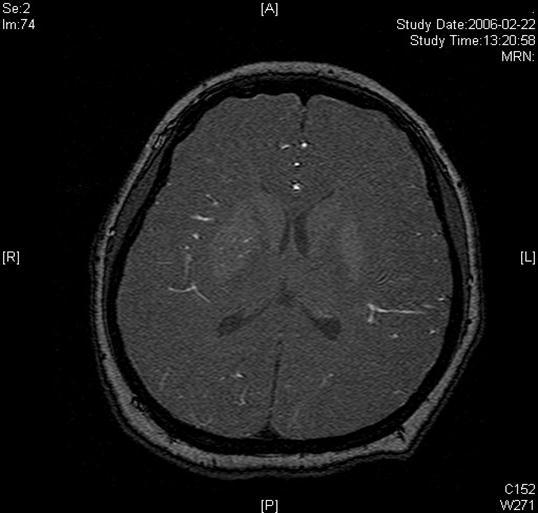

A twenty-nine-year-old female was admitted in Feb, 2006 because of episodic left limb numbness and weakness for half a year. The duration of the episode lasted for a few minutes, seldom over ten minutes. There was an attack every several days. She denied special medical history. She did not live in the pandemic area of Leptospirosis. Her blood pressure was 110/65mmHg and body weight was 51 kilograms. Physical examination found no abnormality. Magnetic resonance angiogram (MRA) (Feb 22) showed severe stenosis in the M1 segment of right MCA. In the source images of MRA, an oval area of abnormal signal in the right basal ganglion was found (Figure 1). Blood routines, coagulation tests, blood biochemistry tests, and C-reactive protein level were normal. The anti-nuclear antibody (ANA), anti-extractable nuclear antigen (ENA) antibodies, and anti-neutrophil cytoplasmic antibodies (ANCA) were negative. Serologic test for Syphilis was negative. Blood sedimentation rate (ESR) was 20 mm/h, and the level of anti-streptolysin O microtitration test (ASO) was 395 IU/ml (0-200 IU/ml). Digital subtraction angiography (DSA) detected severe stenosis (95%) in M1 segment of the right MCA, and the distal blood flow was compromised (Figure 2). The patient was given aspirin 100mg/d, clopidogrel 75mg/d and atorvastatin 20mg/d since Feb 26. Due to the finding of high ASO level, she was given penicillin (4 million IU, bid) for a week. Because of disagreement between the consulting physician and the interventional radiologist, her angioplasty and stenting was delayed till Mar 21 on her request. During the waiting time, her attacks did not reduce. Before the operation, besides the combination of aspirin and clopidogrel, subcutaneous low molecular weight heparin (LMWH) (5000U, q12h) was given for 5 days. After a complete diagnostic evaluation of the blood vessels with DSA, stenting was performed with a stainless steel stent 2.75 mm in diameter by 1.5 cm in length (PC, Abott Company) at the presure of 7 atm. No compromise of perforating branches was found and residual stenosis was less than ten percent on angiography (Figure 2).

Figure 1.Lesion in the right basal ganglia displayed in the source image of MRA

Lesion in the right basal ganglia displayed in the source image of MRA